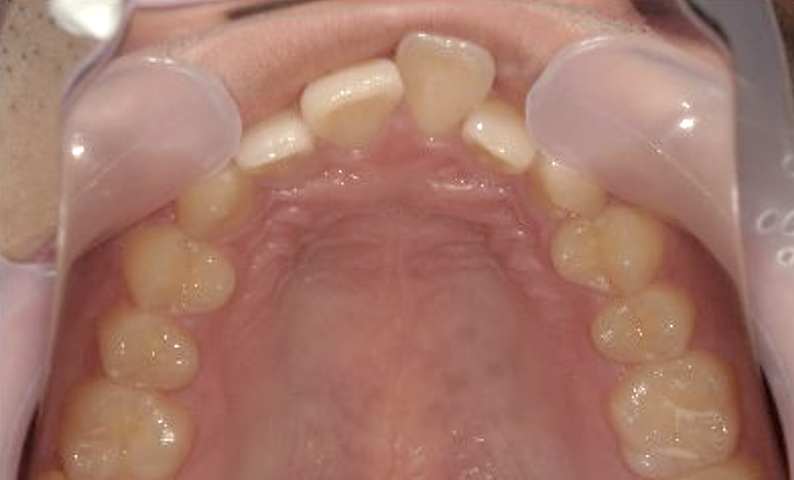

症例_001 上下顎の部分矯正

治療期間:12ヶ月金額:54万円+税女性前歯のガタガタ逆八の字

| Before | After |